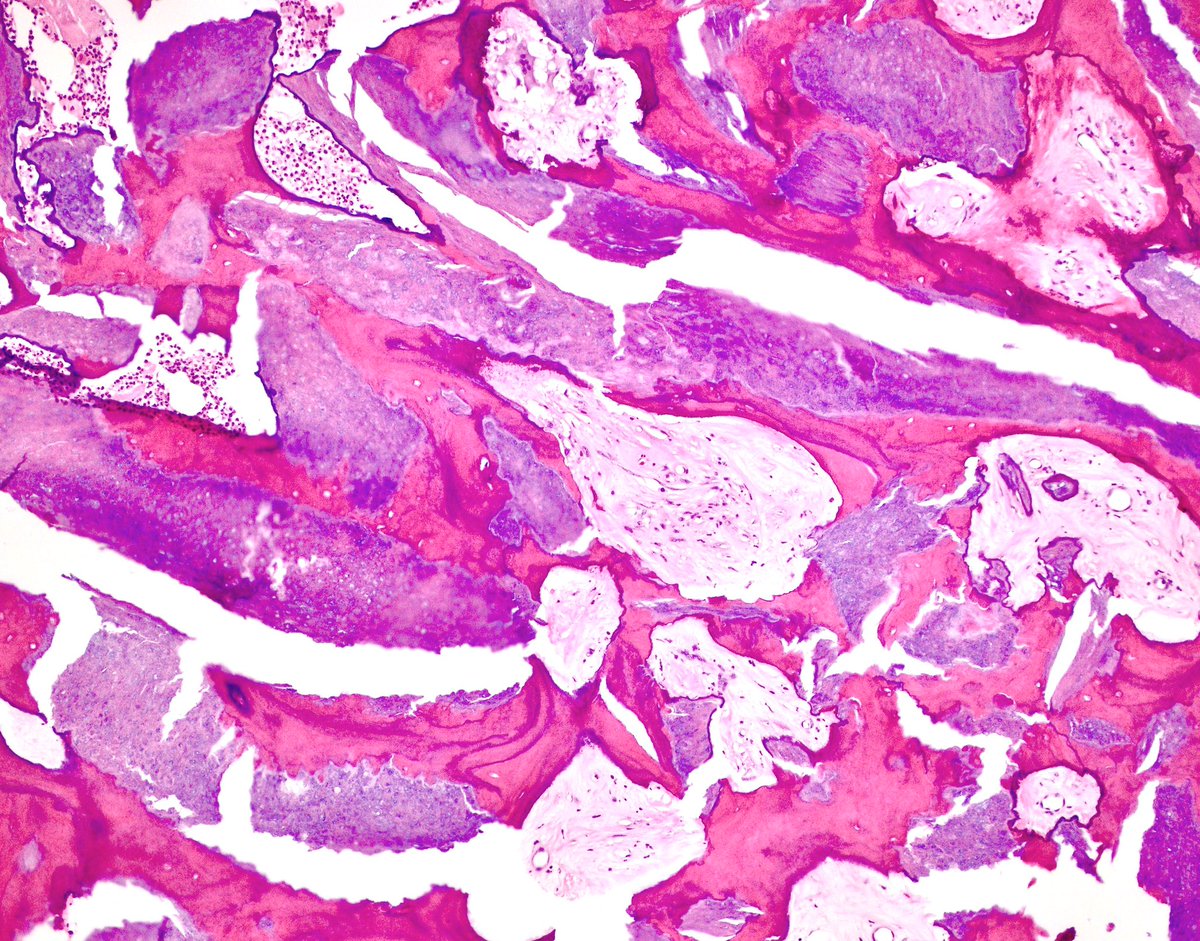

Striking example of the rare Mucinous Tubular Spindle cell carcinoma (MTSCC) of the kidney

#GUPath#GUPS#kidney#Cancer@UMichPath#pathologypic.twitter.com/UNwjNBPpW0